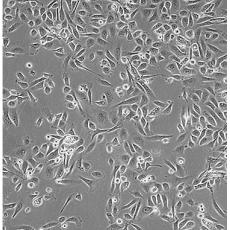

中文名稱 人前列腺癌細(xì)胞

組織來源 前列腺癌;骨髓轉(zhuǎn)移;男性

生長特性 adherent

形態(tài)特征 epithelial

細(xì)胞描述 PC-3源于一位62歲白人男性IV級(jí)前列腺腺癌患者的骨轉(zhuǎn)移灶;有低水平的酸性磷酸酶活性和5-α-睪酮還原酶活性。